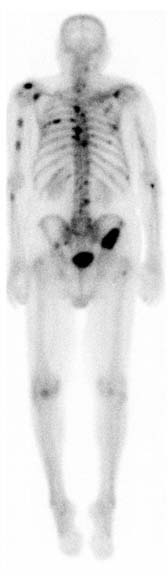

When it's time to do your scan, you'll be asked to lie on a table where a large camera called a scanner will measure how much of the radionuclide has been absorbed by your bones. You will be asked to move into different positions and hold very still so the camera can take pictures of all sides of your body. You may need to lie still for as long as 30 minutes. The radionuclide collects more in parts of the bone that are breaking down and repairing themselves, these show up darker on the scan and are called hot spots. A digital picture is made by the scanner which a radiologist or specialist uses to work out what's happening.

The amount of radionuclide that's absorbed depends on the amount of growth or activity in the bone.

- Test results are normal when the radionuclide is spread evenly throughout your body. This means that you're unlikely to have any major bone problems.

- Areas that absorb little or no amount of radionuclide appear as dark or "cold" spots. This could show a lack of blood supply to your bone, or certain types of cancer.

- Areas of bone growth absorb more radionuclide and show up as "hot" spots in the pictures. These may mean you have a problem (eg, cancer, a fracture or an infection).

Image credit: RadsWiki(external link) via Wikimedia Commons

Image credit: RadsWiki(external link) via Wikimedia Commons